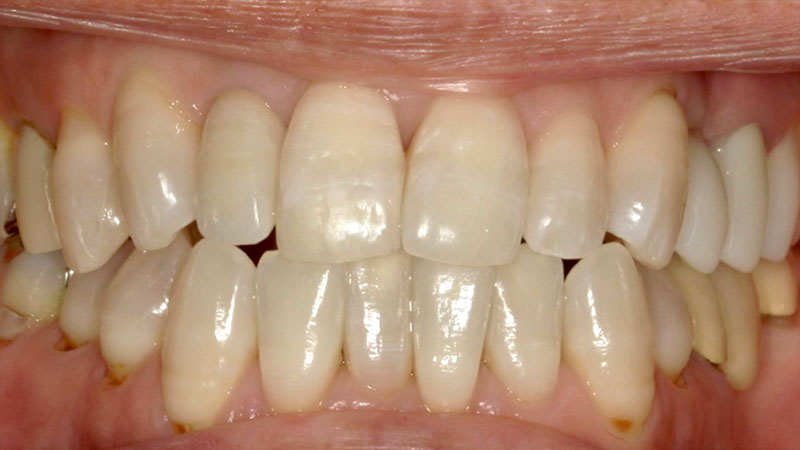

オフィスホワイトニング症例

オフィスホワイトニング症例をご紹介します。

今回させていただいたオフィスホワイトニングはプラチナコースになります。

通常のオフィスホワイトニングの3回コースをお得にできます。

また、シミ止めと歯を強くするコーティングもさせていただきます。

| 患者様 | 50代男性 |

|---|---|

| 主訴 | 歯を白くしたい |

| 治療費 | 総額44,000円(税込) ※当時の価格より現在は費用が上がっております |

| 治療期間 | オフィスホワイトニング3回 約1ヶ月 |